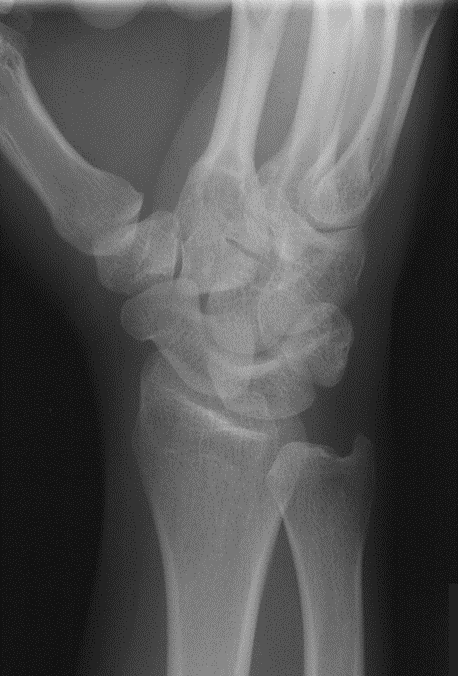

Colles Fracture

Distal radius fracture with fragment displaced posteriorly; often from fall on outstretched hand.

Routine Projections of the Wrist (4)

Lateral

Posteroanterior (PA)

45° Semi-pronated Oblique

45° Semi-supinated Oblique

What projection was performed to produce this image? What is the structure best demonstrated?

Radial side of carpal bones aka trapezium, scaphoid, lunar NOTCH

Lateral Wrist

Lunate